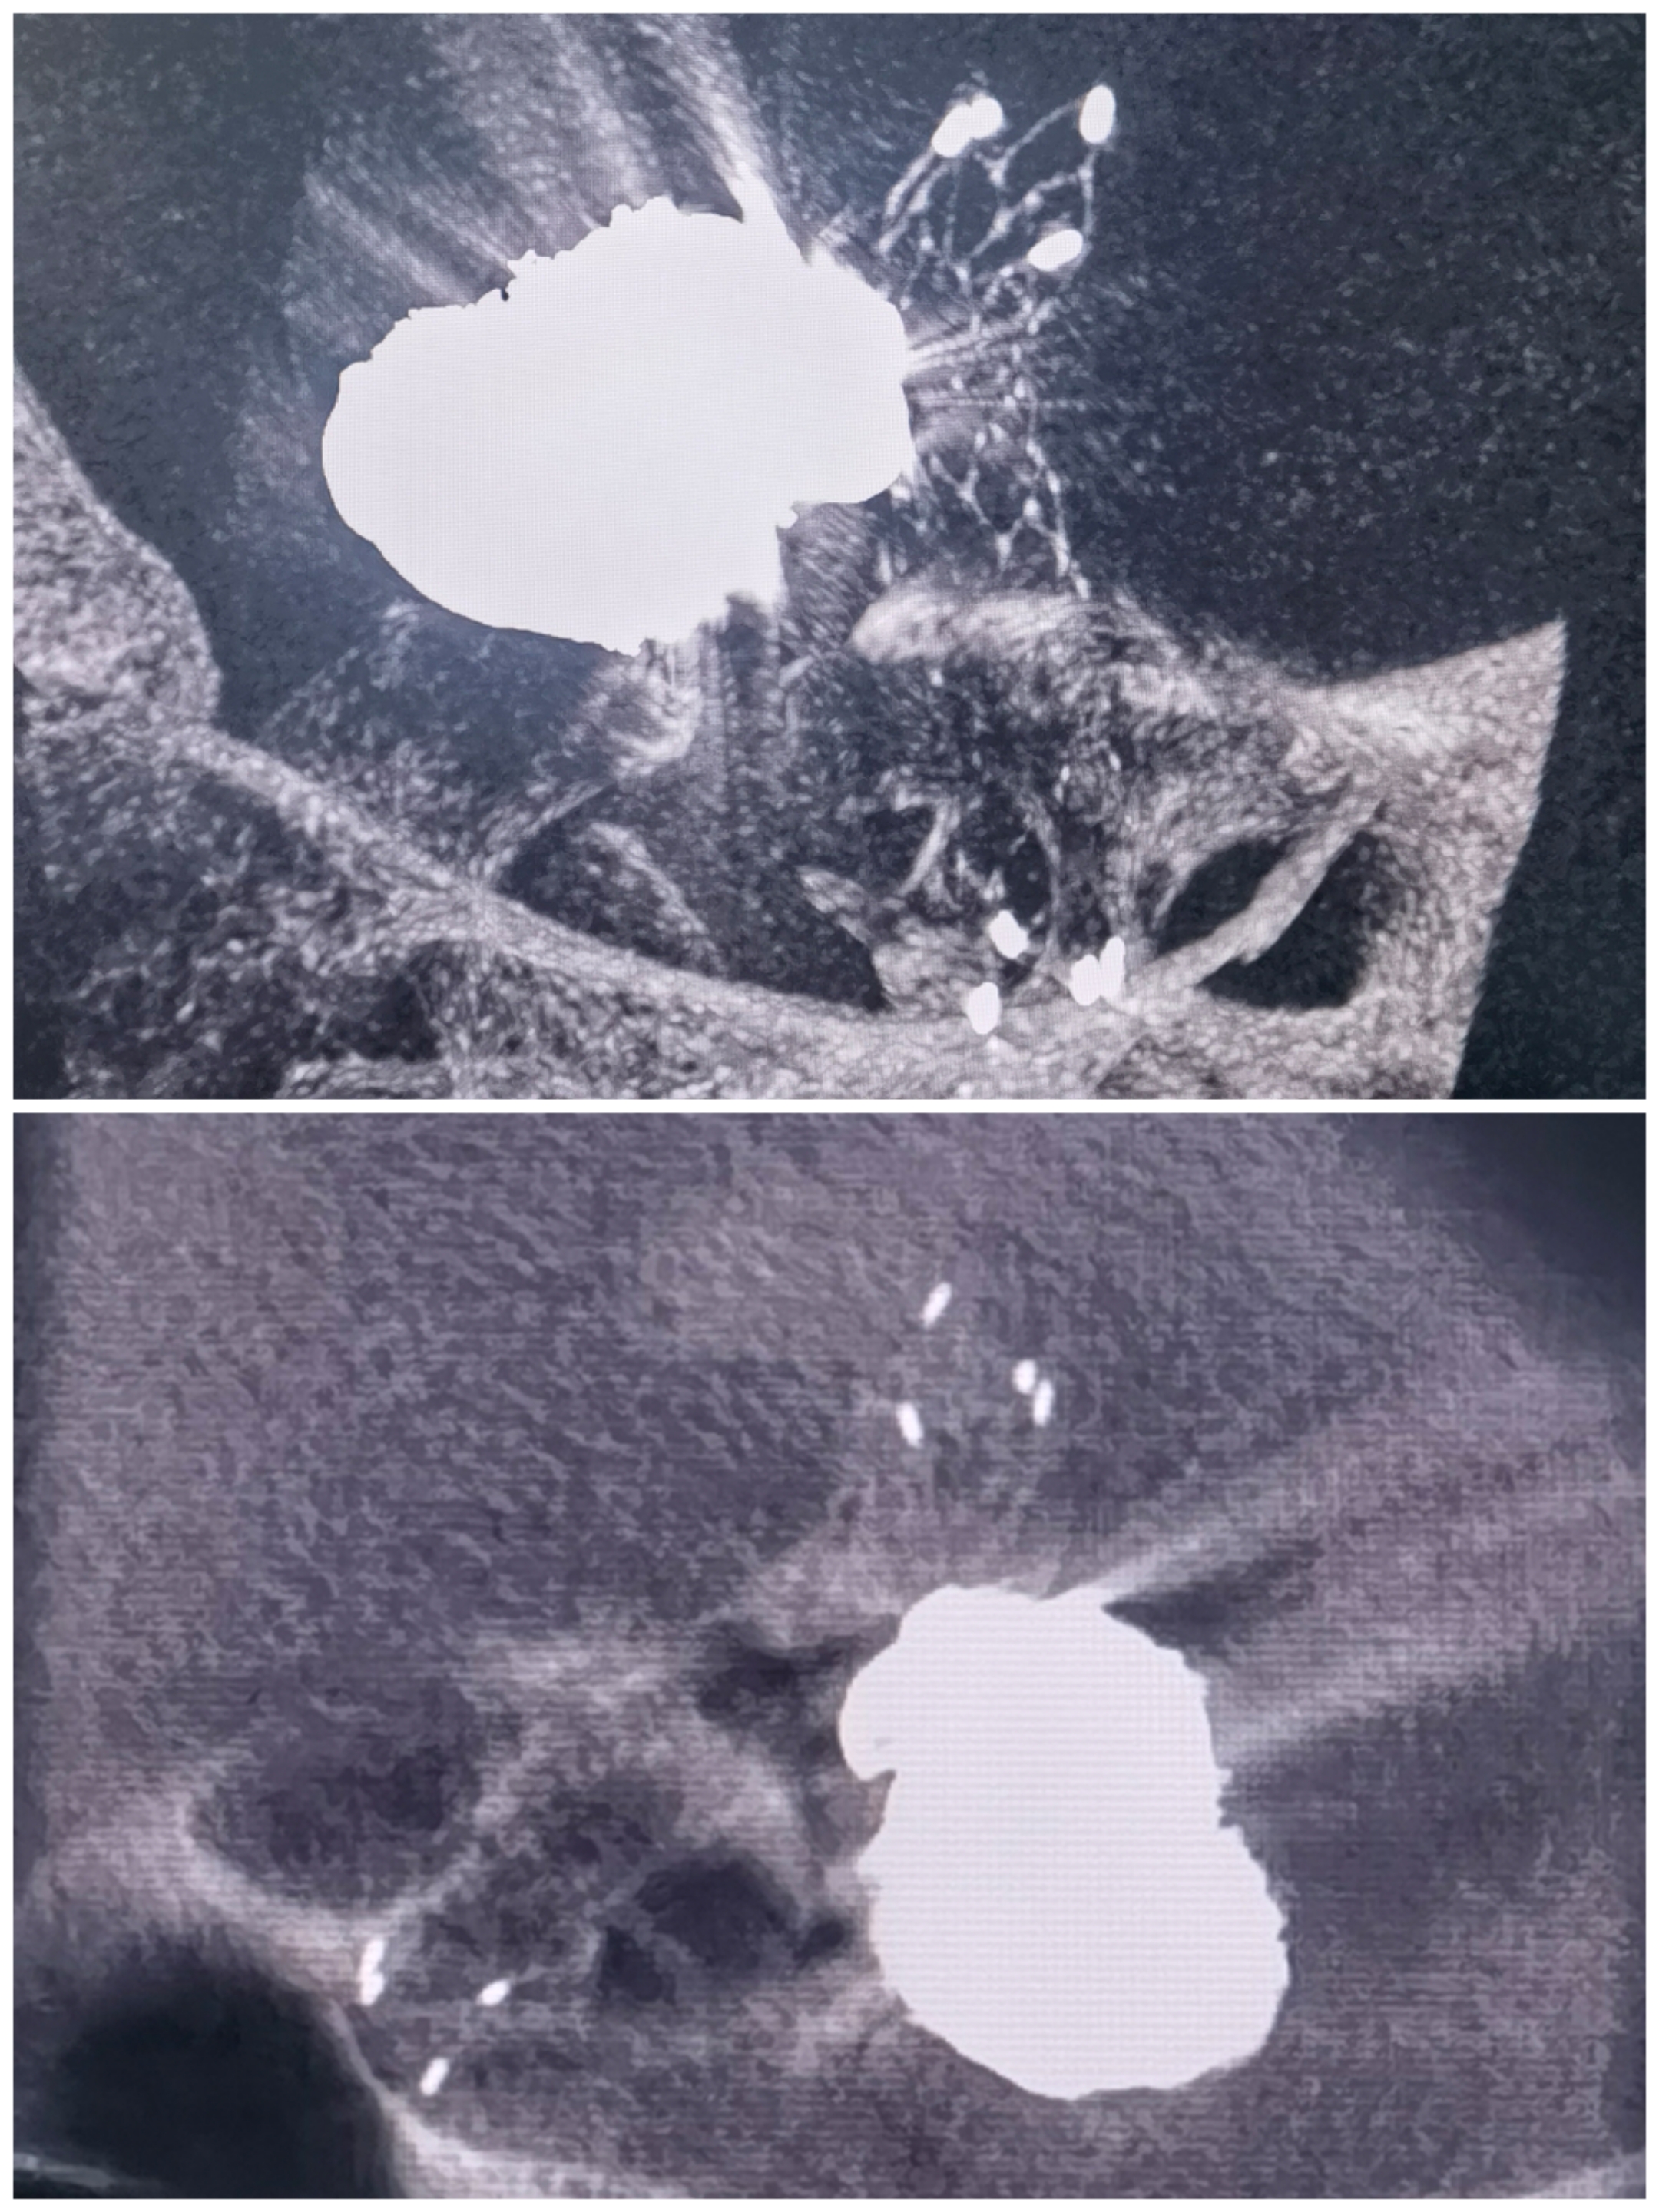

患者一般情况:老年女性,SAH入院,Hunt-Hess分级2级

术前头颅CT提示SAH,Fisher分级2级

术前CTA提示:左侧后交通不规则动脉瘤

左侧颈内正位造影

左侧颈内侧位造影

左侧颈内3D造影

3D重建提示不规则后交通动脉瘤,多发子囊,细小后交通自瘤颈口发出

术前计划:拟支架辅助+双微管栓塞。

术程:0.088指引导管到位,支架导管及双微管到位,双微管交替栓塞+支架辅助

栓塞术后:动脉瘤栓塞致密,后交通动脉仍保留